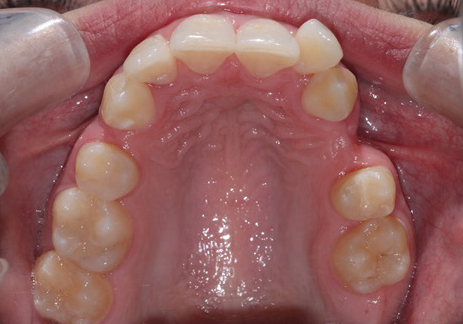

Clinical Orthodontics: Trouble Closing Extraction Space?